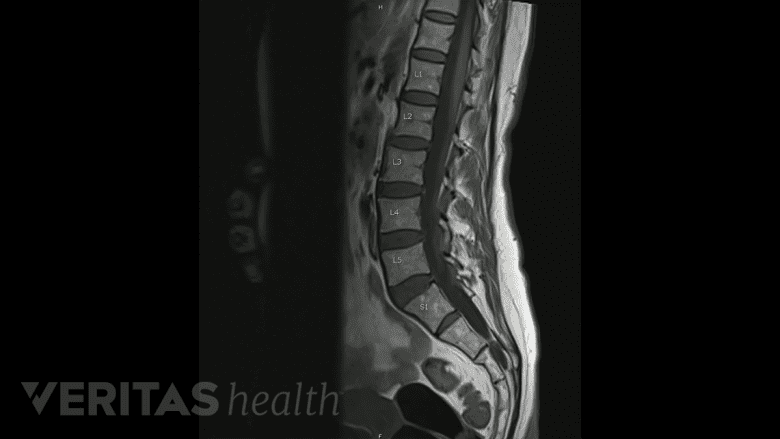

On an MRI scan, a degenerated disc appears darker than a healthy disc.

On an MRI scan, a degenerating disc will appear black or dark, as opposed to a healthy disc that has a lighter appearance. Disc degeneration can be present without causing any symptoms of lower back pain; for example, an MRI of an older person may be expected to show degeneration in all the discs without causing degenerative disc disease.